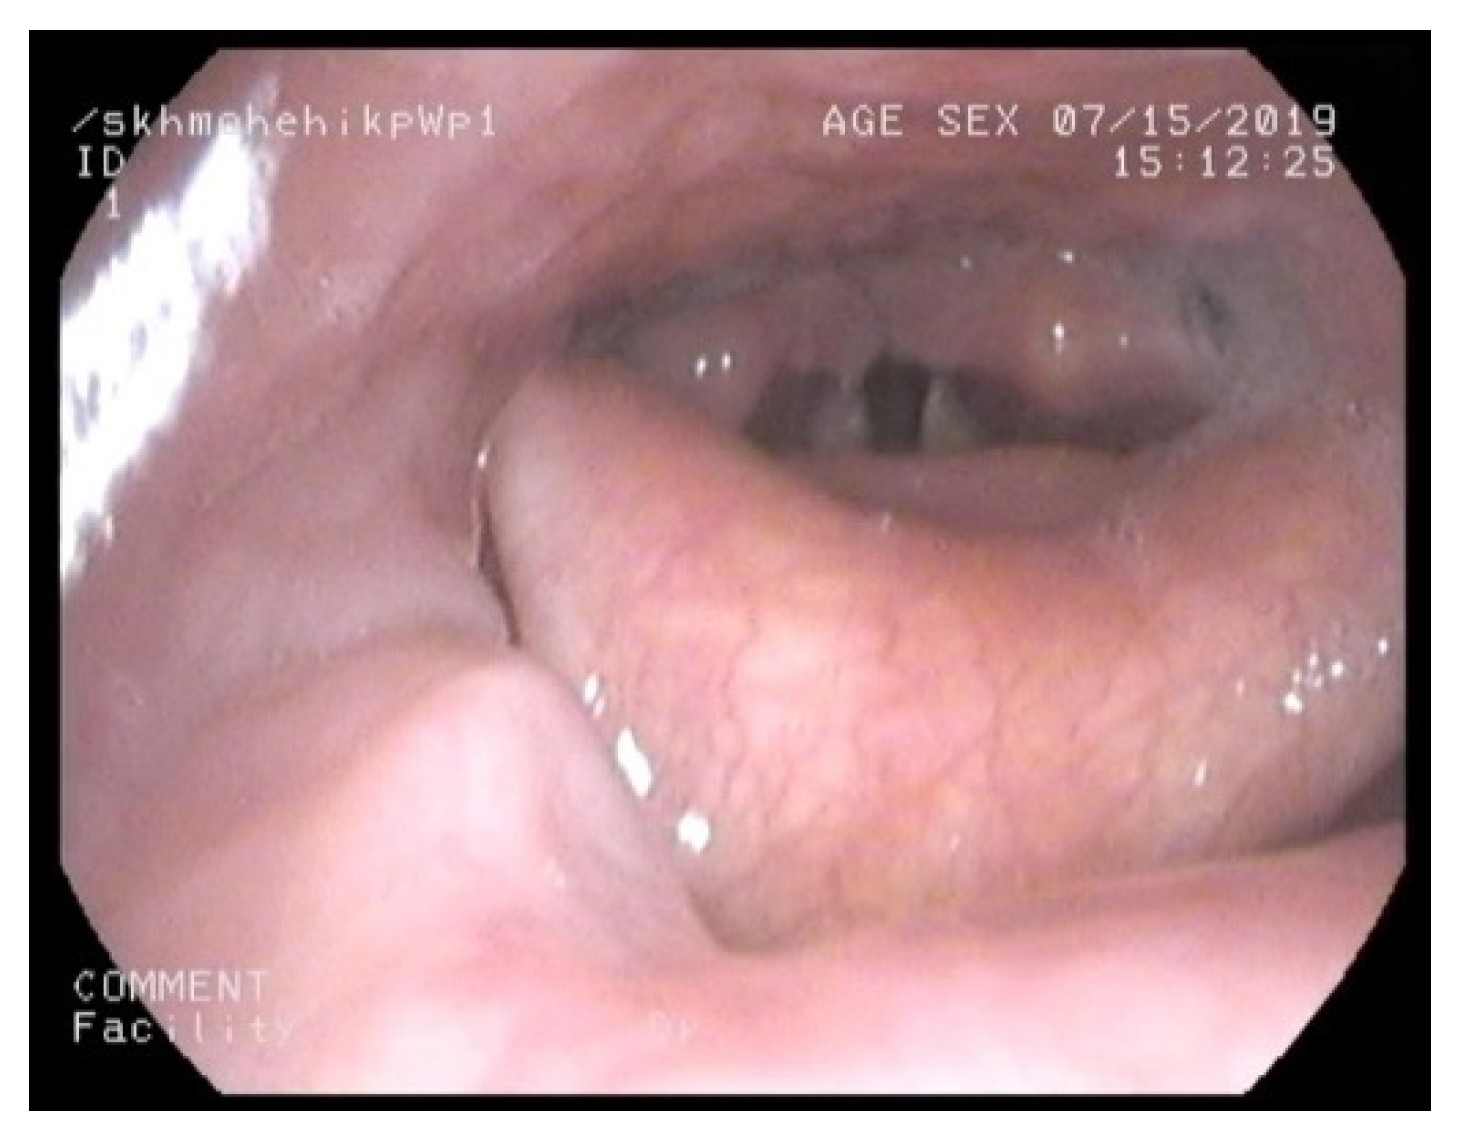

3.1. Nasendoscopy

- Epiglottis bulkiness on nasendoscopy / scan.

- Normal= 0 score (filling less than less than 1/3 of oropharynx)

- Mild bulkiness = 1 (filling 1/3–1/2 of oropharynx)

- Moderate bulkiness = 2 (filling 1/2 to complete oropharynx)

- Severe bulkiness = 3 (filling the entire oropharynx) *

- Supraglottis bulkiness on nasendoscopy/scan.

- Normal= 0 score (filling less than less than 1/3 of supraglottis)

- Mild bulkiness = 1 (filling 1/3–1/2 of supraglottis)

- Moderate bulkiness = 2 (filling 1/2 to complete supraglottis)

- Severe bulkiness = 3 (filling the entire supraglottis) *

- Glottis bulkiness on nasendoscopy.

- Normal = 0 score (filling less than less than 1/3 of glottis)

- Mild bulkiness = 1 (filling 1/3–1/2 of glottis)

- Moderate bulkiness = 2 (filling 1/2 to complete glottis)

- Severe bulkiness = 3 (filling the entire glottis) *